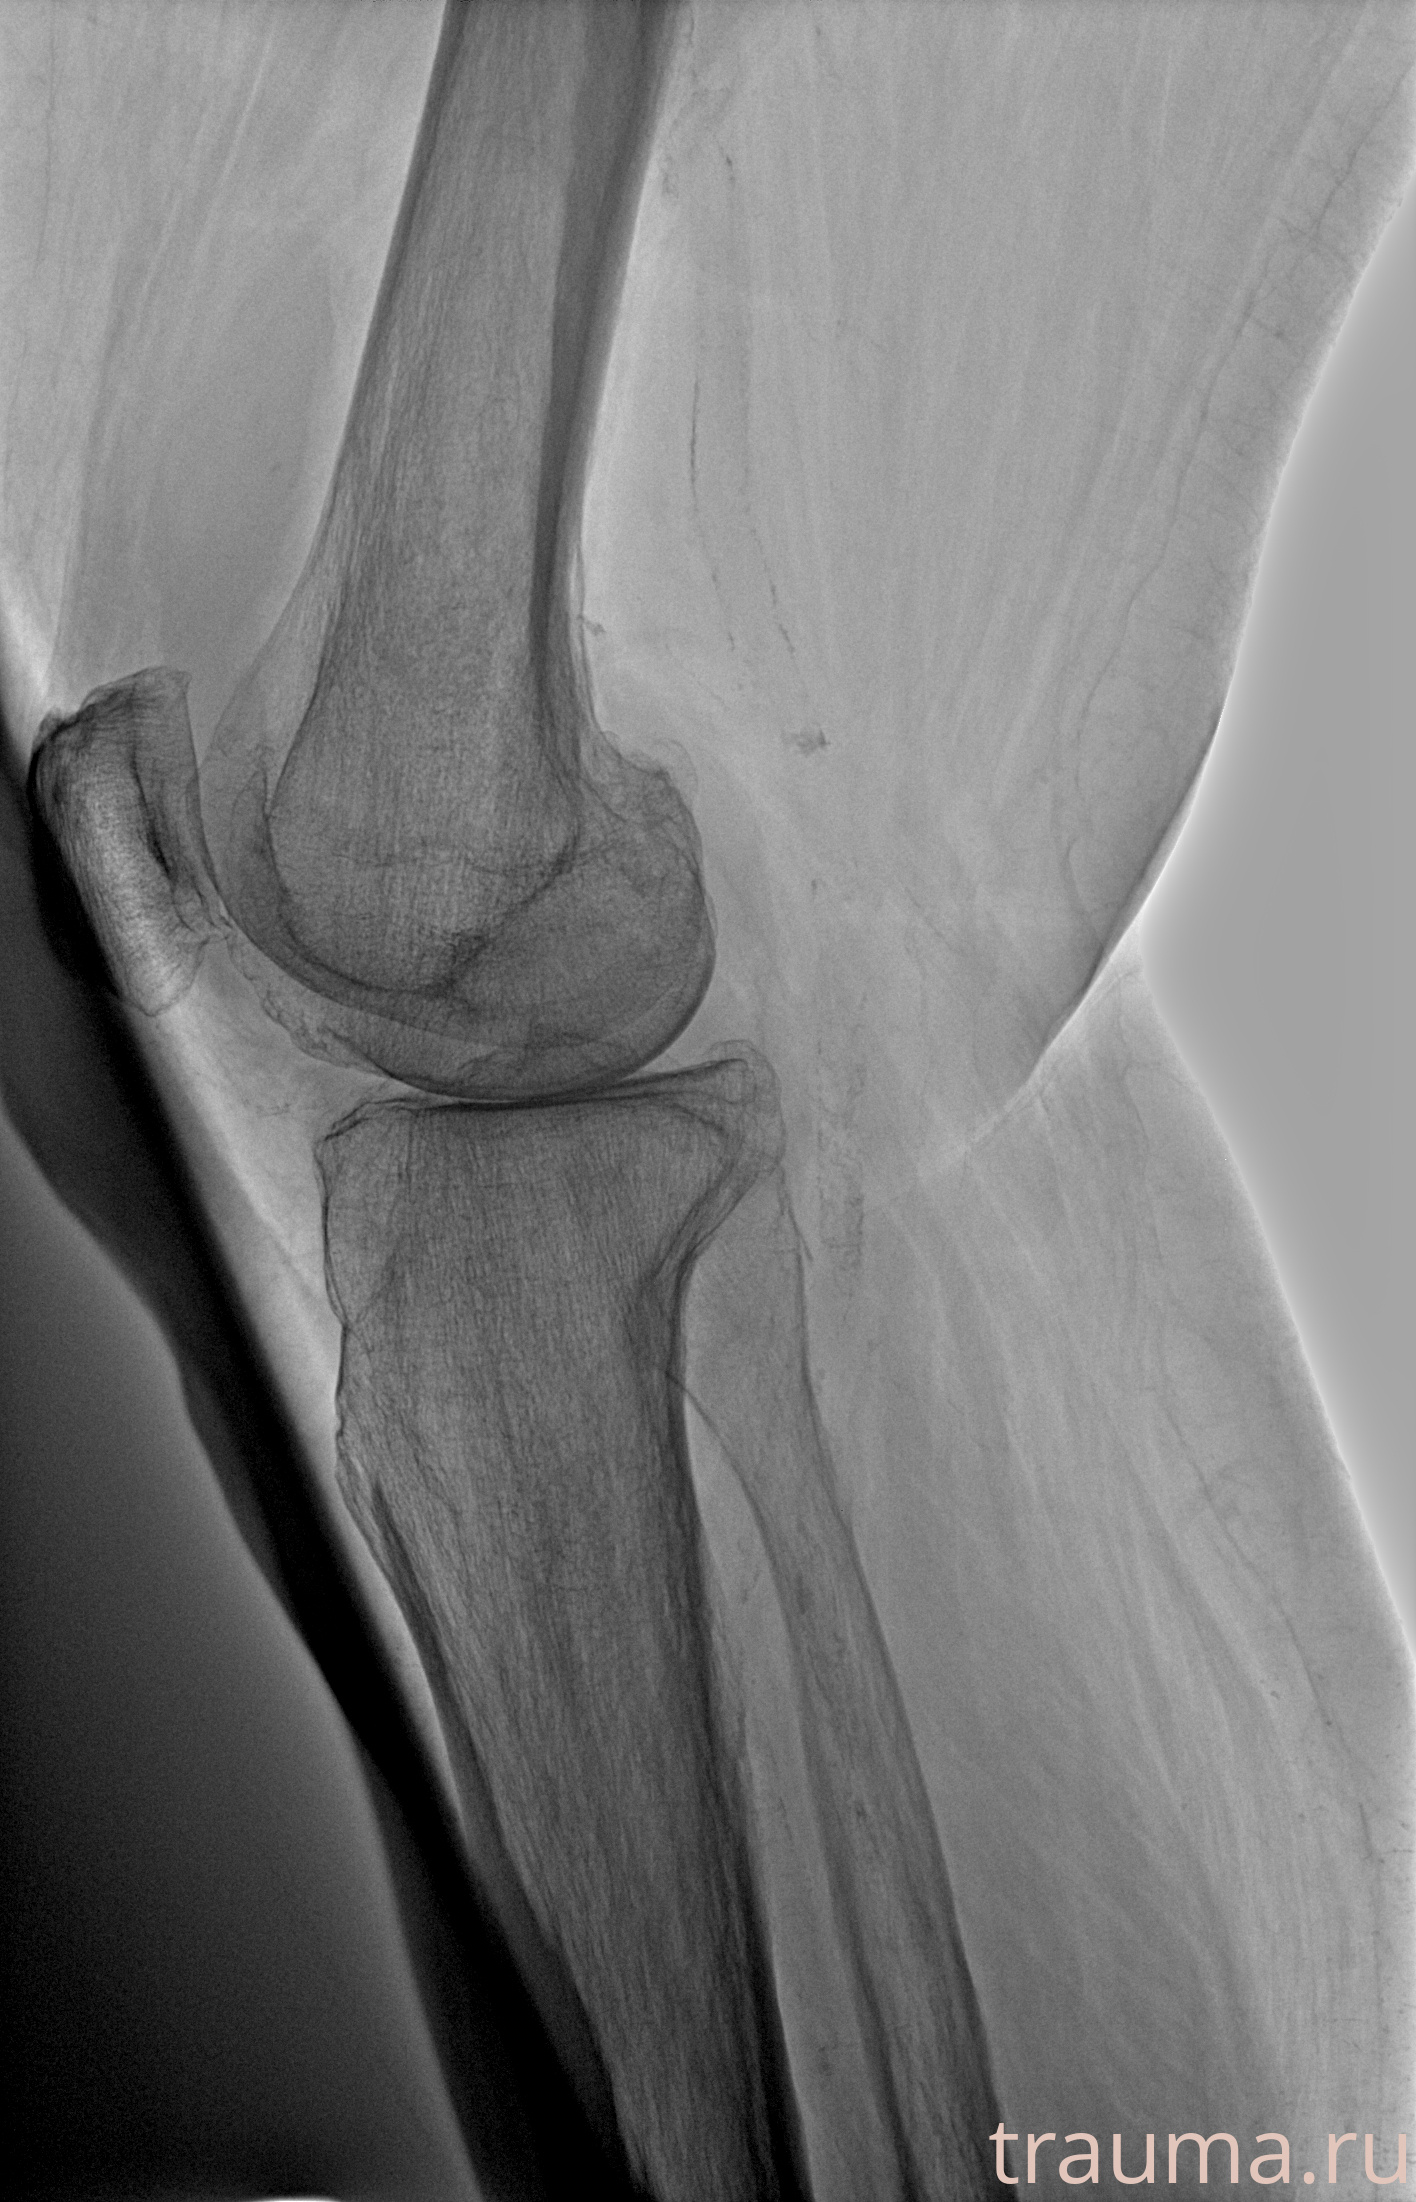

Рентгенограммы

Рентген на дому: по вашему адресу приезжает врач-рентгенолог, травматолог-ортопед с мобильным рентгеновским аппаратом, проводит диагностику травмы или заболевания, делает необходимые рентгенограммы, дает рекомендации по дальнейшему лечению. Получить качественные снимки в домашних условиях возможно благодаря уникальной методике, разработанной МосРентген Центром для института  Склифосовского